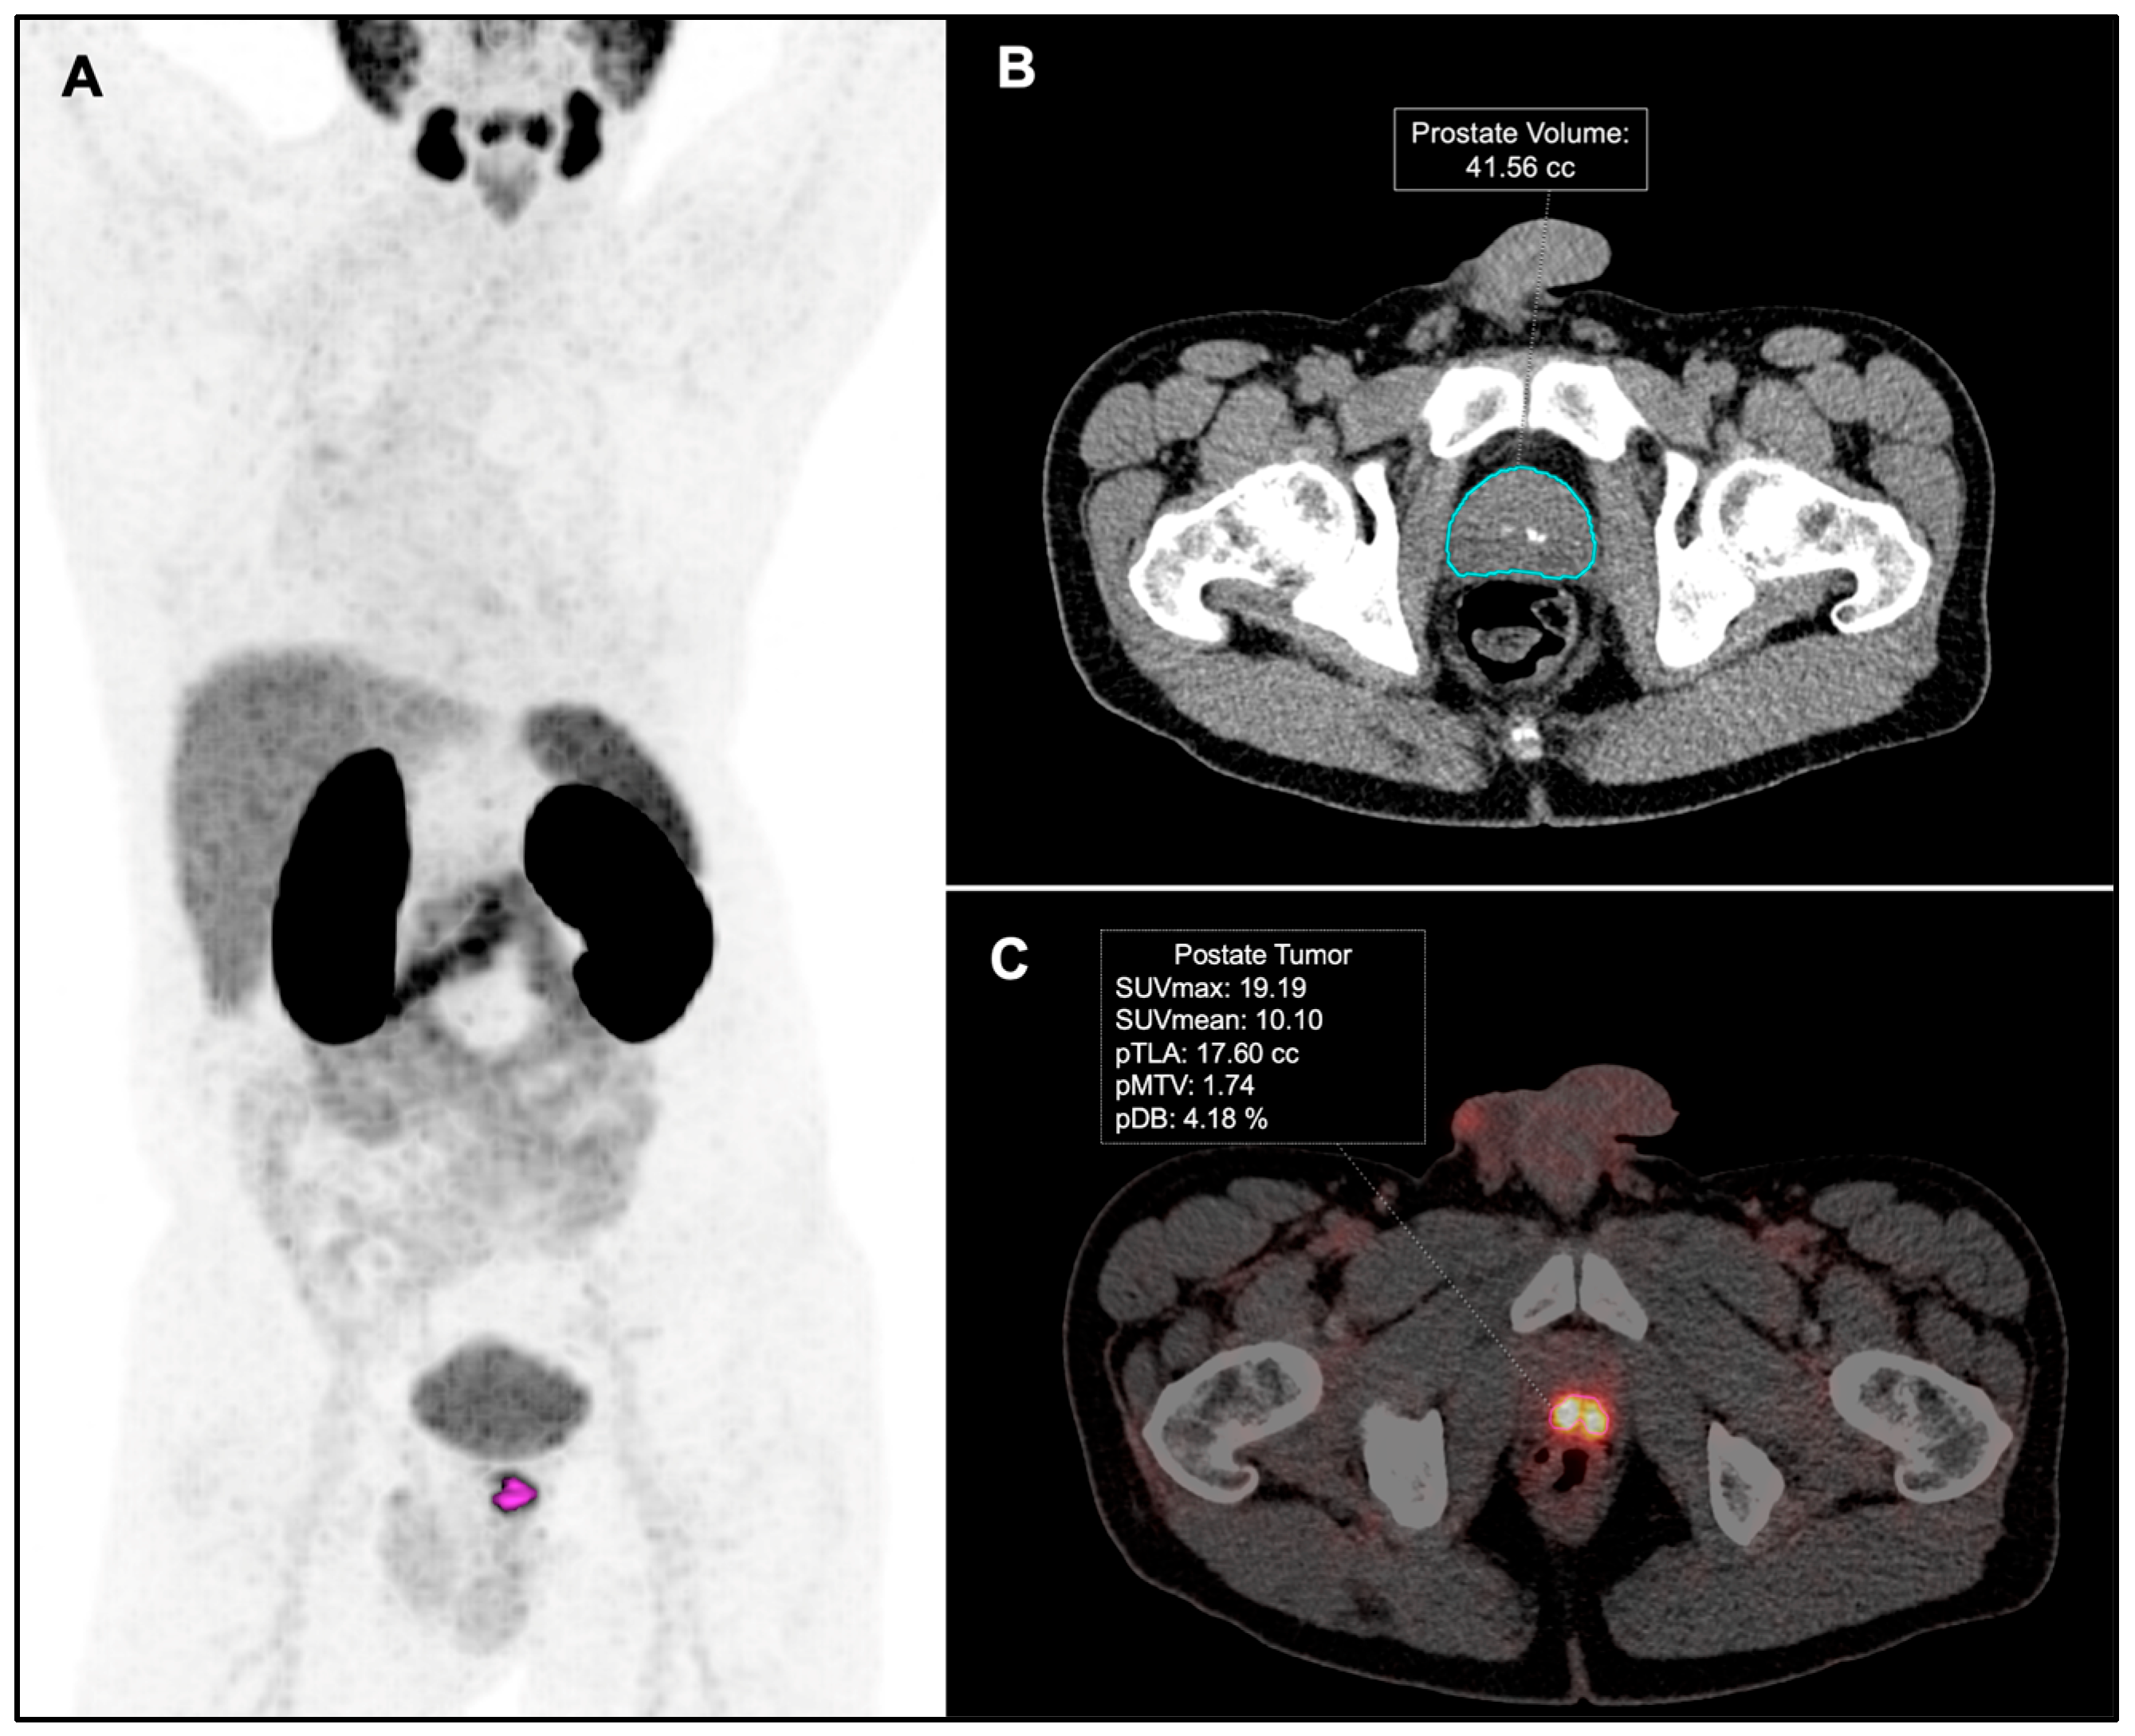

Figure 2.

Exemplary patient with high-risk PCa. (A) PET-PSMA maximum intensity projection. (B) Automatic segmentation of the prostate gland on axial CT images. (C) PSMA-PET metrics in primary tumor.

PSMA-PET metrics in the prostate gland were calculated and named as follows: tumor SUVmax, tumor SUVmean, Prostate Molecular Tumor Volume (pMTV), Prostate Volume (pV), Prostate Total Lesion Activity (pTLA), and Prostate Disease Burden (pDB), which was calculated using the formula (pMTV × 100/pV). In patients with miT3b, the infiltration of the seminal vesicles was included in the prostrate volume-based metrics.

PSMA-PET images were reviewed by two nuclear medicine physicians (MRF and JJR). Tumor and nodal staging on PSMA-PET were reported based on the criteria featured in the E-PSMA guidelines [25]. The quantitative analysis of the molecular parameters from the PSMA-PET imaging was conducted by the second nuclear physician (JJR). A spherical volume of interest (VOI) was drawn in all the pathological PSMA uptake in the prostate gland to encompass the entire target lesion and isoactivity contours were automatically generated. A threshold percentage cut-off range between 40 and 45% was used to provide the best visual contouring of the boundaries of the tumor in the prostate gland, as previously described by other authors [26,27]. Prostate Volume (pV) was obtained through the automated segmentation of the prostate gland on CT images using work-in-progress syngo.via MI General Anatomy Segmentation (Siemens Healthineers, Knoxville, TN, USA) (Figure 2).